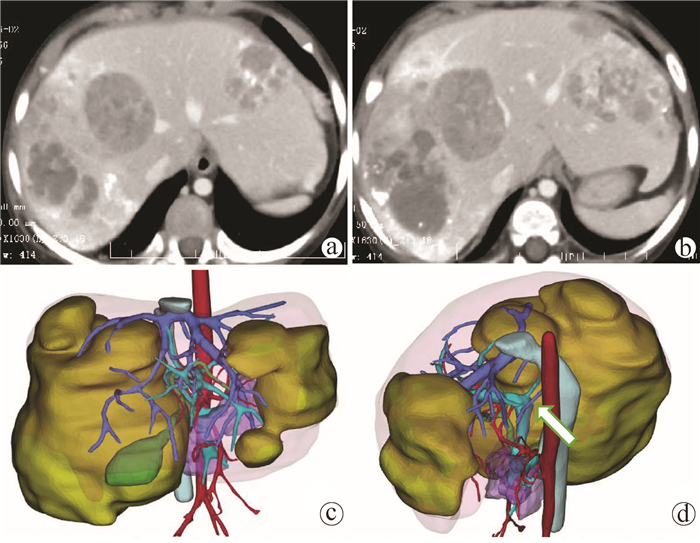

肝脏三维可视化重建技术在儿童复杂肝母细胞瘤肝切除术中的应用价值

赵頔, 叶进冬, 李华丽, 金奎, 刘翔, 李潇然, 段留新, 刘军桂, 吕伟, 段伟宏, 刘全达

2021, 37(9): 2130-2135. DOI: 10.3969/j.issn.1001-5256.2021.09.025

摘要(1333) HTML (406) PDF (3973KB)(68)

摘要:

目的  探讨肝脏三维可视化重建技术在儿童复杂肝母细胞瘤肝切除术中的应用价值。  方法  回顾分析2018年1月—2020年10月于火箭军特色医学中心实施了以根治性切除为目的的肝肿瘤切除术的30例肝母细胞瘤患儿的临床资料,根据术前是否行肝脏三维重建(IQQA-Liver系统)将所有患儿分为三维重建组(n=15)和对照组(n=15),比较2组患儿围手术期临床参数以及短期预后和随访情况。符合正态分布的计量资料2组间比较采用独立样本t检验,不符合正态分布的计量资料2组间比较采用Mann-whitney U检验。计数资料2组间比较采用Fisher确切概率法。  结果  三维重建组较对照组平均年龄更大[(55.7±10.2)月vs (28.2± 2.7)月]、POSTTEXT Ⅲ/Ⅵ期(12例vs 5例)和肝静脉或下腔静脉受累者(11例vs 3例)更多,差异均有统计学意义(P值均<0.05)。所有患儿均顺利完成手术,2组在出血量、手术时间、肝门阻断次数/时间、行肝段及部分肝切除例数方面,差异均无统计学意义(P值均>0.05)。术后中位随访时间9.5个月,三维重建组2例复发,分别于术后10个月和12个月确诊,目前继续化疗中;对照组4例复发,高于三维重建组(P=0.651),其中2例在术后7个月复发接受肝移植存活至今,另有2例复发后短期内死亡。  结论  三维可视化重建技术有助于更安全精准实施复杂儿童肝母细胞瘤肝切除术,尤其是可以使部分POSTTEXT Ⅲ/Ⅵ期患者安全实施扩大肝切除,从而避免行肝移植。